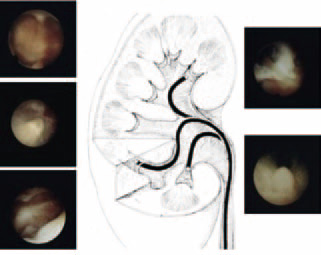

近年来输尿管软镜技术在泌尿系结石微创治疗方式上所占的比例越来越高,已成为治疗上尿路结石的一种重要术式,是腔内泌尿外科发展史上的一个里程碑。它本身可在肾内拐弯,镜体末端拐弯角度可达180度到275度,利用人体自然腔道,更加微创,可以同时处理输尿管上段和肾内结石,目前是2厘米以下肾结石和直径1.5厘米左右输尿管上段结石的主要处理方法,但也有许多2厘米以上结石通过输尿管软镜碎石成功的病例。输尿管软镜技术具有安全,基本无创,并发症少等优点,特别适用于年老体弱及肥胖的肾结石患者。此外,对于一些特殊病例,如孤立肾,马蹄肾,出血倾向,脊柱畸形,肾功能不全,碘过敏,稀有血型(RH阴性血,俗称“熊猫血”)等等的结石患者,输尿管软镜有着独特的优势。